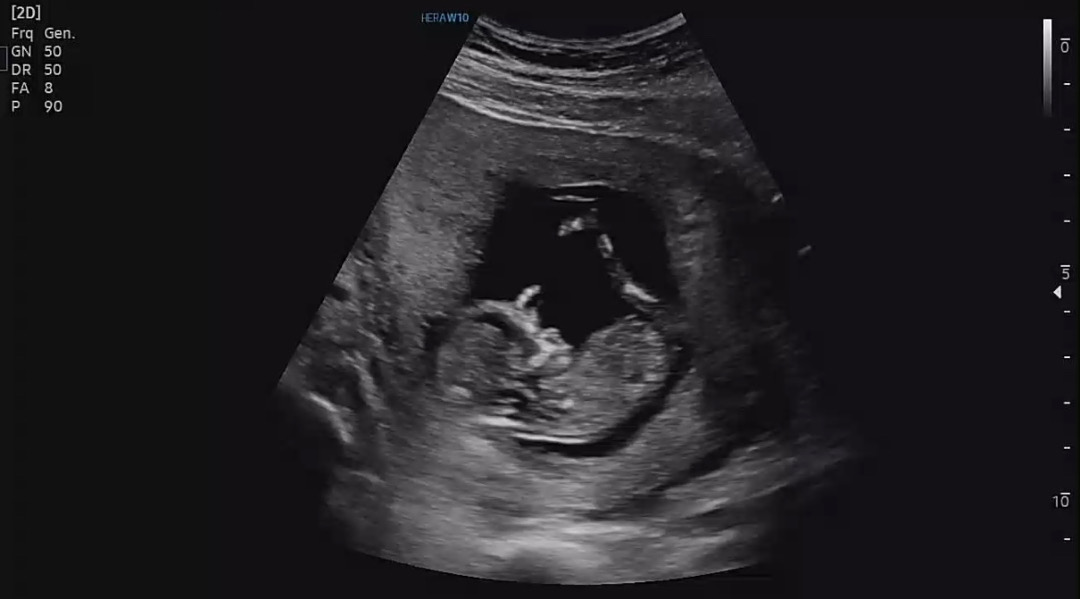

8월 초 예정일이라 드디어 1차 기형아 검사 받았습니다! 다행히 목투명대는 1mm미만이라 다행인듯하네요.. 검사받기 전까지 3주동안 초음파도 안보기도 했고, 그사이 출퇴근 하면서 힘들어서 괜히 걱정도 되었는데 건강하게 지내는 것 같아 너무 안심입니다 ㅠㅠ 이렇게 기다리다보면 출산일도 임박하겠죠? 저처럼 걱정이 많으신분이 있으시다면… 걱정 마시고 좋은 생각만하면서 지내시길 바랍니다🥹